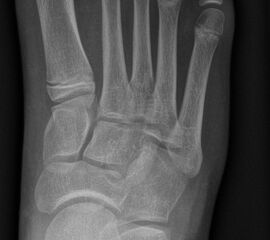

Knick-Senk-Platt-Fuß Korrektur mit dem Canalis Tarsi Spacer

In der Korrektur des schmerzhaften, aber flexiblen Knick-Senk-Fußes oder Plattfußes ist die Schraubenarthrorise mit einem Sinus tarsi oder besser bezeichnet als Canalis tarsi Spacer und alternativ mit einer Calcaneus-Stopp-Schraube seit vielen Jahren ein etabliertes Verfahren und führt zu einer kompletten Korrektur von flexiblen Knick- und Plattfuß-Fehlstellungen (Abb. 7). Die nötige Schnittlänge über dem Sinus tarsi beträgt für beide Verfahren 1 cm.